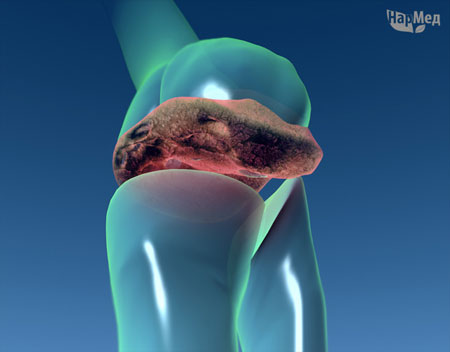

Воспалительные изменения возникают прежде всего во внутренней, синовиальной оболочке сустава. Развивается синовит, при этом в суставной полости часто скапливается воспалительный выпот — экссудат. Патологический процесс может распространяться на другие структуры сустава — хрящ, эпифизы костей, составляющих сустав, капсулу сустава, а также на околосуставные ткани — связки, сухожилия, сумки. Артрит одного сустава носит название «моноартрит», двух-трех суставов — «олигоартрит», более трех суставов — «полиартрит».

Течение артритов при различных заболеваниях различно. Так, для ревматизма и подагры характерно быстрое, в течение нескольких дней или недель, полное обратное развитие всех симптомов. При ревматоидном артрите, болезни Бехтерева, псориатическом артрите воспаление суставов чаще имеет хроническое течение; со временем в патологический процесс могут вовлекаться все новые суставы, наблюдаться разрушение (деструкция) хряща и суставных отделов костей, развиваться стойкие деформации суставов и даже полная их неподвижность (анкилоз).

Ревматоидный артрит – хроническое заболевание суставов, он имеет постепенно прогрессирующее течение, иногда прерывающееся ремиссиями (периодами временного улучшения). Воспаление сустава характеризуется его опуханием, болезненностью и иногда появлением красноты. Как уже было сказано, при ревматоидном артрите могут воспалятся и околосуставные ткани – связки и мышцы. Хроническое воспаление сустава приводит к разрушению суставного хряща и возникновению деформации сустава, что в свою очередь, нарушает его функцию – возникают боли при движении и тугоподвижность.

Сустав пораженный артритом

Сустав состоит из суставных поверхностей костей, покрытых хрящом, суставной капсулы, суставной полости с небольшим количеством жидкости.

Воспаление, прежде всего, возникает во внутренней — синовиальной оболочке сустава, развивается первично под воздействием различных факторов (инфекции, травмы, опухоли).

Патологический процесс может распространяться на другие структуры сустава: хрящ, эпифизы костей, составляющих сустав, капсулу сустава, а также на околосуставные ткани — связки, сухожилия и сумки. Вторично воспаление возникает как ответная реакция на патологические изменения в костных элементах сустава.

Хроническое воспаление сустава приводит к разрушению суставного хряща и возникновению деформации сустава, что в свою очередь, нарушает его функцию — возникают боли при движении или поднятии тяжестей и тугоподвижность.